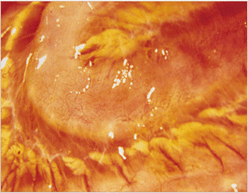

임상증상6

사진56 사진57 사진58

설명56 설명57 설명58